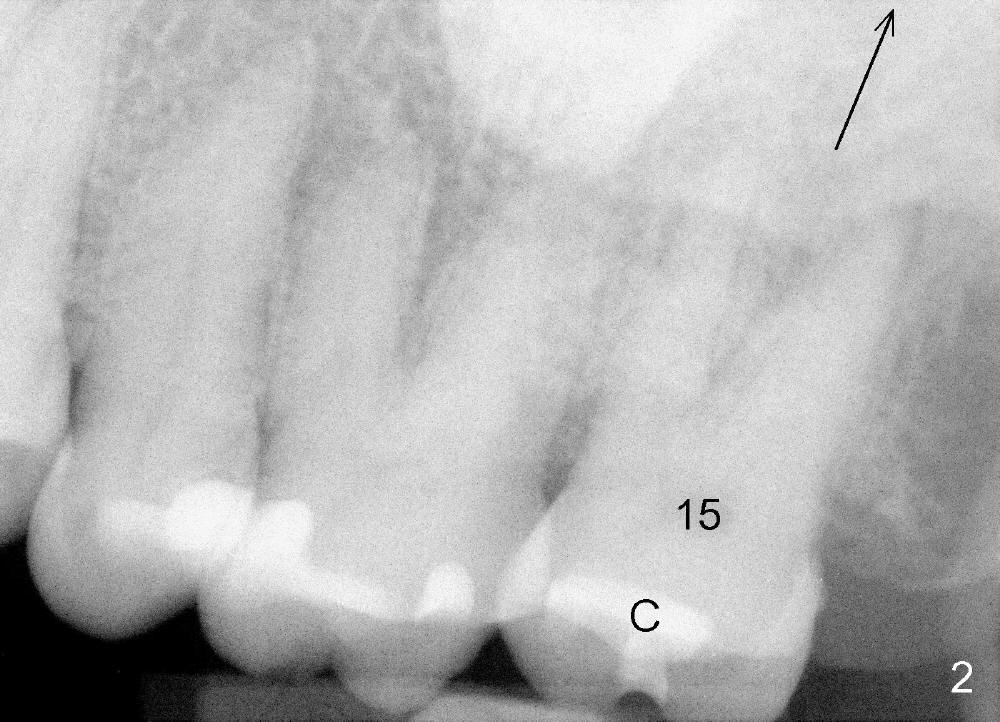

A 57-year-old lady presents for abscess buccal to the tooth #15 (Fig.1 A). Mesial and distal to the occlusal composite (Fig.2 C) is a crack line. In addition to long furcated roots, the upper border of the bone is not shown in this preop PA (arrow). Fig.3 is taken to show a thin septum surrounded by the mesiobuccal (MB), distobuccal (DB) and palatal (P) sockets (Fig.3). Osteotomy is initiated in the septum by 1.2 and 1.5 mm pilot drills, followed by 2,3,4 mm rounded tapered osteotomy at the depth of 17 mm. Nose blowing test is carried out after each step with negative result. Stability is achieved when a 4.5 mm tap is inserted at 17 mm, but the upper end of the tap is not visible (Fig.4,5). When a 5 mm tap is placed, stability is decreased, probably because the coronal end of the septum starts to break down (due to expansion). To re-gain stability, the 5 mm tap needs to go deeper. A 6 mm tap also achieves satisfactory stability at 20 mm. When the tap is removed, there is no air leakage. A 6x20 mm implant is placed with insertion torque > 60 Ncm; the upper end of the implant is still out of view in PA (Fig.6). Another problem is that the implant needs to go deeper to obtain sufficient occlusal clearance. The lower first molars and the 2nd premolars are missing. A panoramic X-ray has to be taken to show the apical end of the implant: ~ 3 mm into the sinus (Fig.7 ^). The maxillary tuberosity appears to grow downward (arrow). In other word, the tooth #15 appears to have been intruded due to overloading.